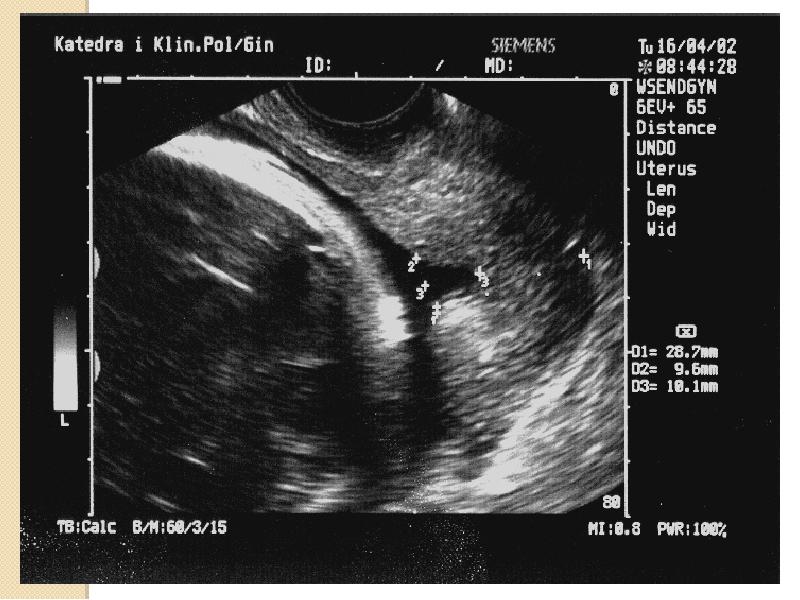

- 45. Niewydolność cieśniowo-szyjkowa Badanie USG Średnia długość szyjki macicy 38-42mm Długość

- 46. Niewydolność cieśniowo-szyjkowa Badanie USG przez powłoki brzuszne: wymaga wypełnienia pęcherza moczowego.

- 47. Niewydolność cieśniowo-szyjkowa Badanie przezpochwowe: pęcherz moczowy musi być opróżniony. należy zidentyfikować